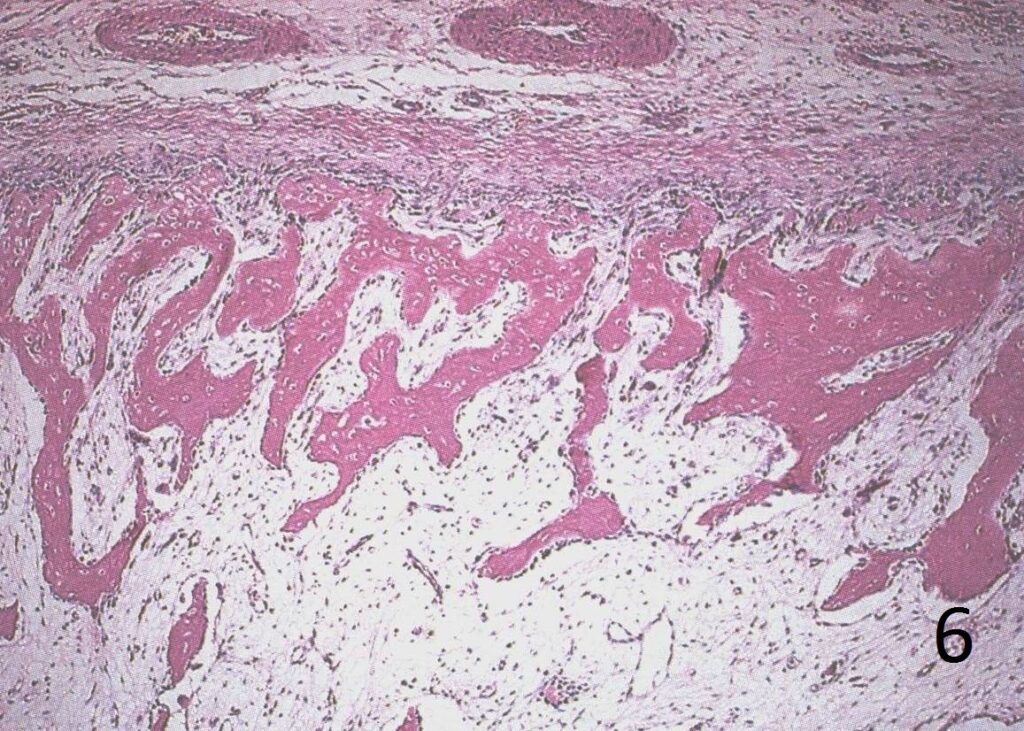

Microscopic

• Very cellular stroma combined with immature new bone formation, possible few mitotic figure (Fig. 5, 6, 7)